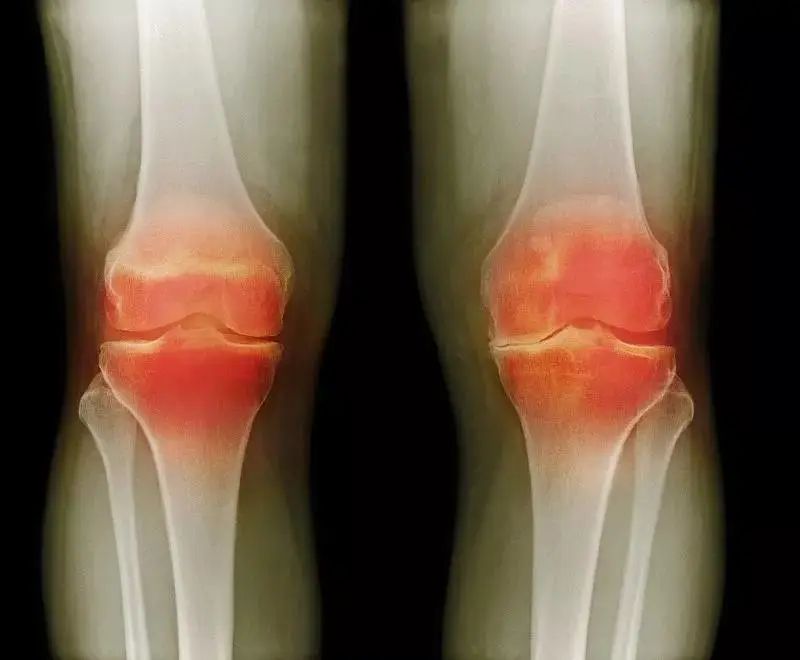

骨关节炎(osteoarthritis, OA)是一种退行性和进行性的疾病。临床表现为缓慢发展的关节疼痛、僵硬、肿胀、活动受限和关节畸形等,包括关节软骨退化损伤、关节边缘和软骨下骨反应性增生。年龄、身体素质、运动损伤是导致骨关节炎主要病因。传统治疗方法中,以非药物治疗和药物治疗为主。均仅能暂时缓解症状而不能改善骨关节炎发病机制或逆转骨关节炎进程。因此,人们希望能够找到一种更加方便可靠、创伤更小、疗效更佳的治疗方法,用来改进现有治疗手段的不足。随着医学及相关领域的迅速发展,再生医学利用干细胞以及细胞因子发挥治疗效应,已逐渐成为 一种新的治疗0A的手段。